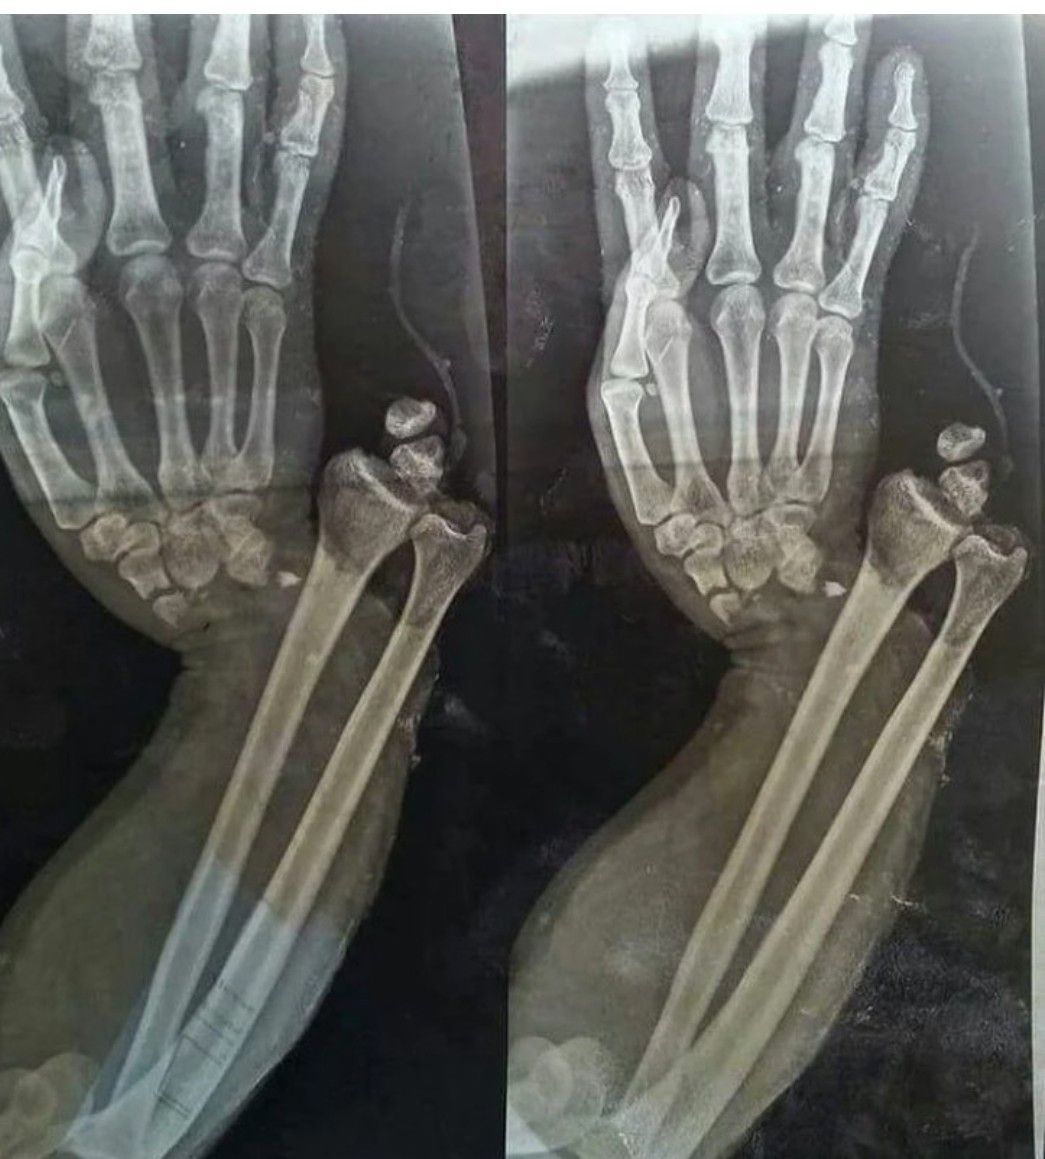

Open Fracture Dislocation of the Wrist

What might be the cause?